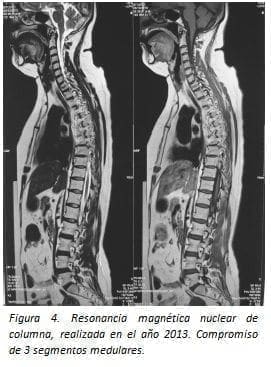

Los estudios de imagen datan desde el inicio de su cuadro clínico: en 1990, se realizó una tomografía axial computarizada cerebral y de médula espinal que se reportaron como normales; en el 2013 se practicó estudio de resonancia magnética cerebral no se observan lesiones de espectro E. múltiple (figuras 4 y 5).